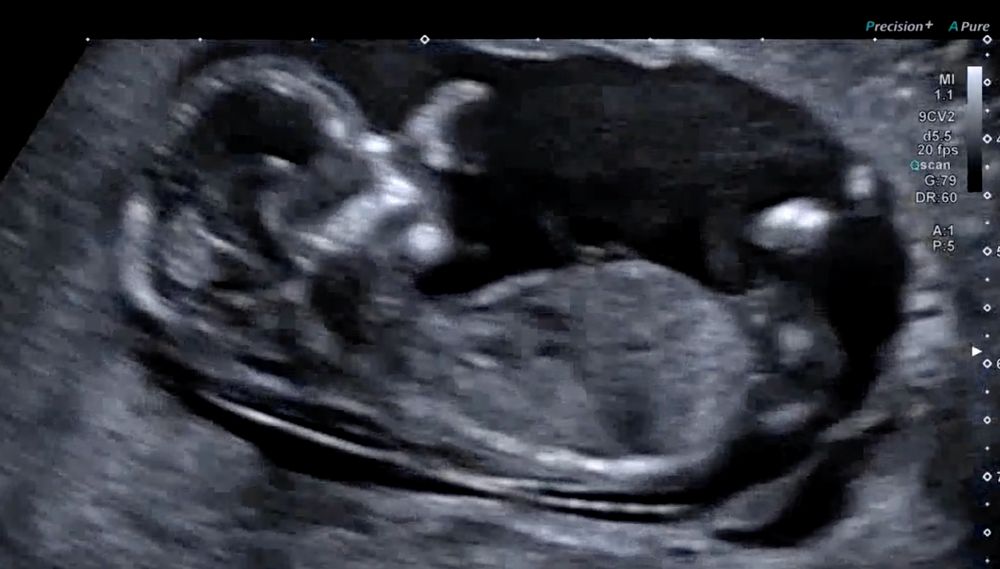

На фото - сосет палец, на видео видно было совсем хорошо.

Вот мы и добрались до второго триместра!!! Ура! Мне все так же ооочень плохо - тошнит, болит голова и все время сплю, но очень много хороших новостей за неделю. Были на скрининге - узи бесплатное и потом на платное сходили, сдали кровь на скрининг и нипт - все результаты идеальные. Твп 1.8 (1.7 над другом узи) все руки ноги посмотрели что на месте все косточки, сердце (143 пульс), почки, мочевой, кровоток в пуповине. На втором узи ребёнок был очень активный, сосал палец!!! И теперь мы знаем кого мы ждём - мальчик!!! Буду одна принцесса дома 😇 можно начинать вязать одеялко и крохотные вещички. Какая большая радость ждать малыша!